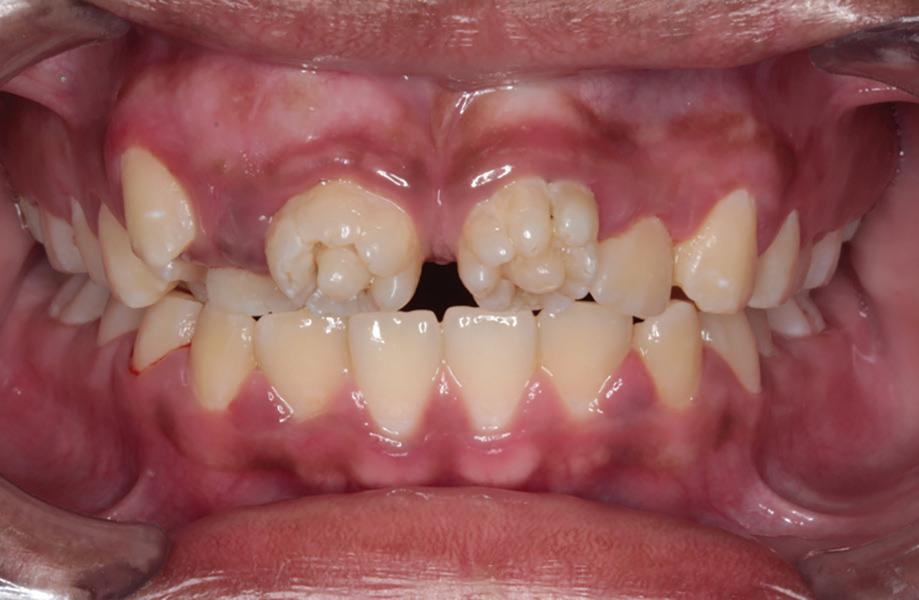

A healthy 10-year-old boy, accompanied by his mother, sought treatment of his mandibular right first molar because of pain in response to cold stimuli but reported no spontaneous pain in this tooth. Clinical examination revealed a carious lesion involving the occlusobuccal surfaces, and the tooth also appeared hypomineralized on the affected surfaces (Fig 1). The tooth responded positively to sensitivity tests, including the electric pulp test and cold test (Endo-Frost, Coltene), and there was no lingering pain or pain on percussion. A preoperative radiograph showed a large carious lesion extending to the pulp, incomplete root formation, and no pathologic periapical lesions (Fig 2). Therefore, the initial preoperative diagnosis was reversible pulpitis. The patient and parent were informed of possible pulp exposure, and VPT treatment after pulp exposure was explained in detail. Written consent for VPT was obtained from the parent.

of a mandibular right first molar with caries affecting the occlusobuccal surfaces, which appear hypomineralized.

Fig 1. Preoperative clinical photograph